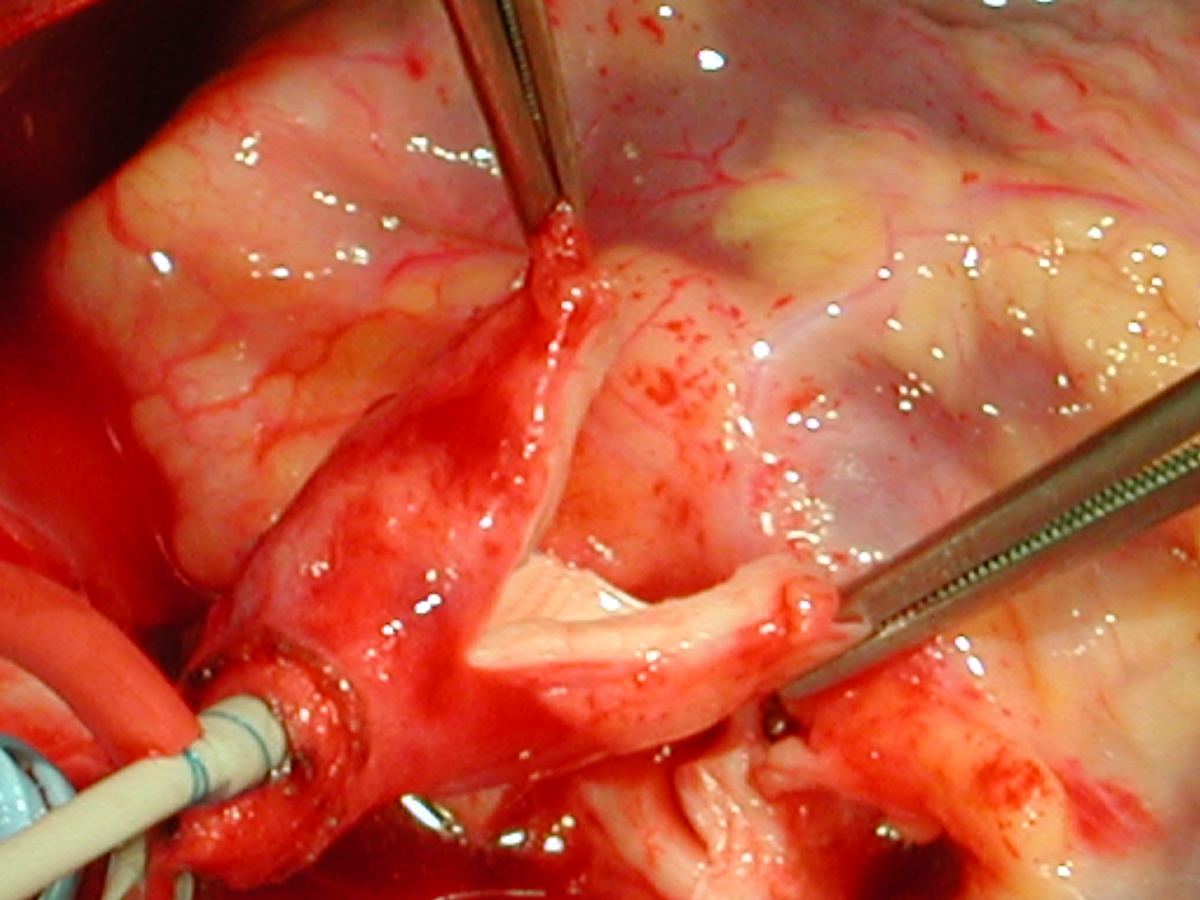

Figures 20 & 21: Third incision has been made to the right of the left coronary orifice. They yellow plastic suture boot on the pickup is pointing out the left coronary orifice. Figures 22 & 23: Proximal ascending aorta now opens widely, revealing the right and left coronary orifices and the normal trileaflet aortic valve below.